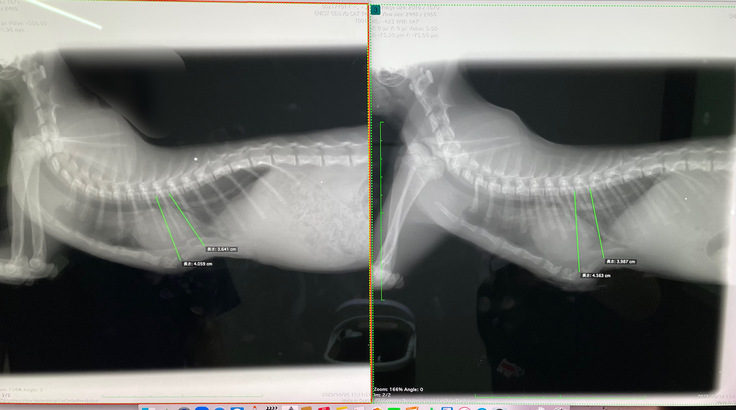

8/26(土)術後8回目の診察

本日はコルセットを外してから

1週間が経ったので、レントゲンを撮り

経過を見ていただきました。

3〜4mmほど戻ってしまっていましたが、

これ以上はおそらく戻らないだろう、とのことです。

心臓の位置も問題ありませんでした。

再手術しなくてはいけないほどでもないので、

来週またレントゲンを撮り、

戻っていなければ引き続き様子見ということになります。

【左 本日】 【右 8/19】